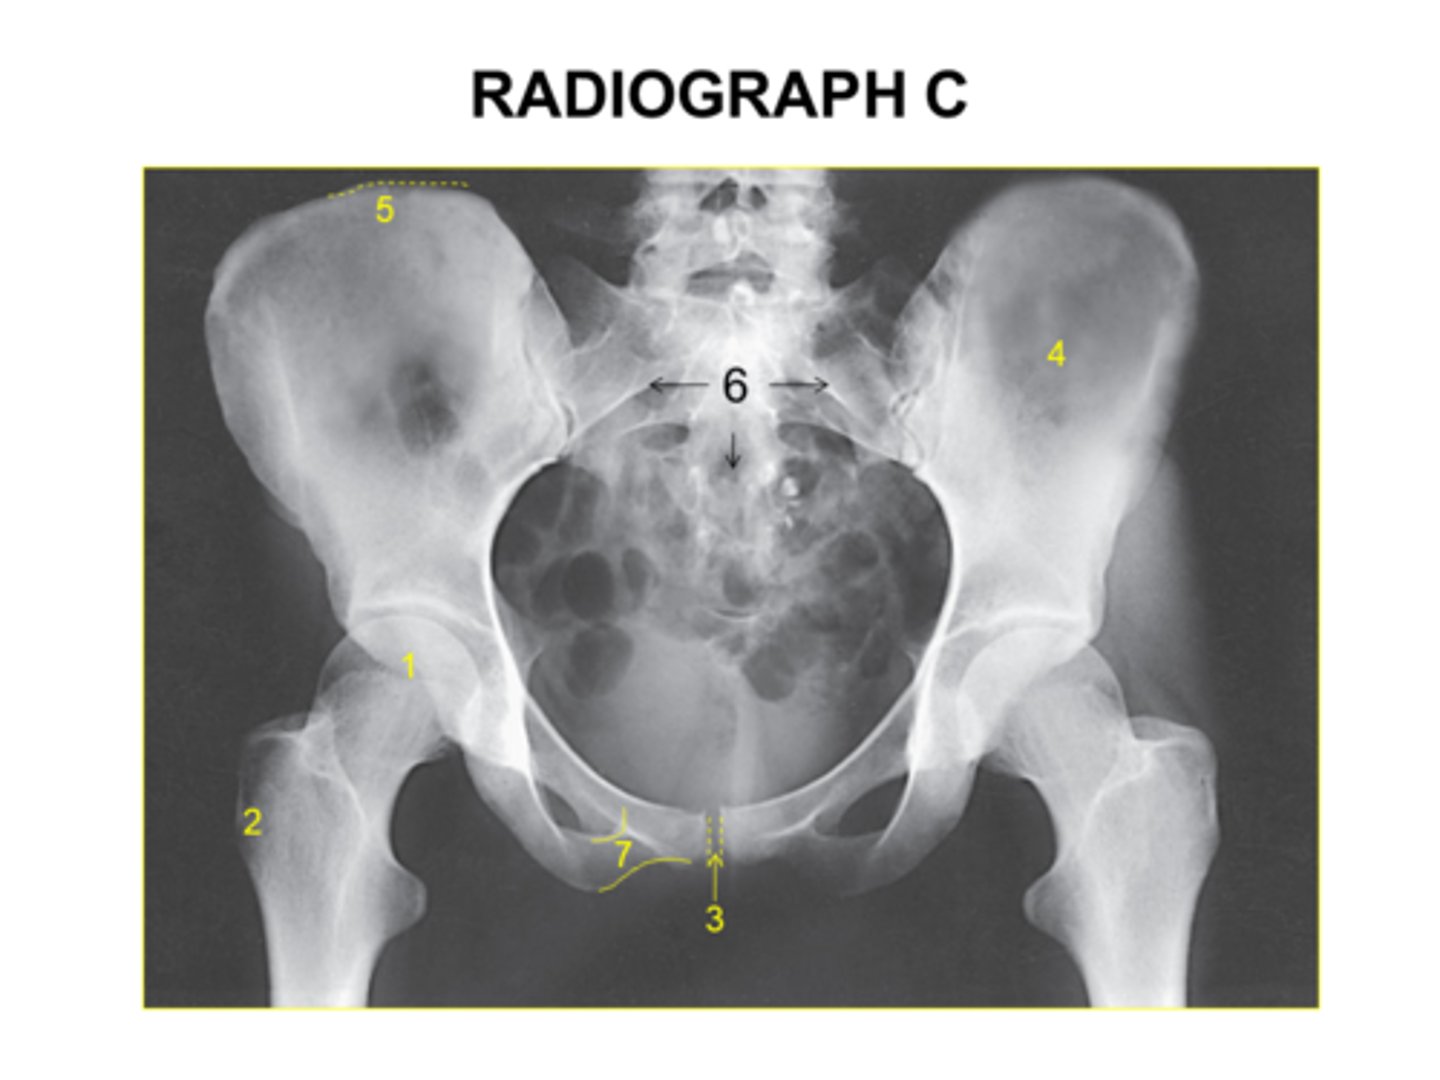

Identify the anatomy marked A:

Pubis bone

Head of the femur

Femoral neck

Ischial tuberosity

Coccyx

The anatomy marked with #6 is the:

Acetabulum

Lesser trochanter

Obturator foramen

Greater trochanter

Ischial spine

Identify the anatomy marked with #7:

Pubic symphysis

Pubic bone

ilium

Is this pelvis rotated?

Yes

No

I'm not sure

The anatomy marked with #3 is the: